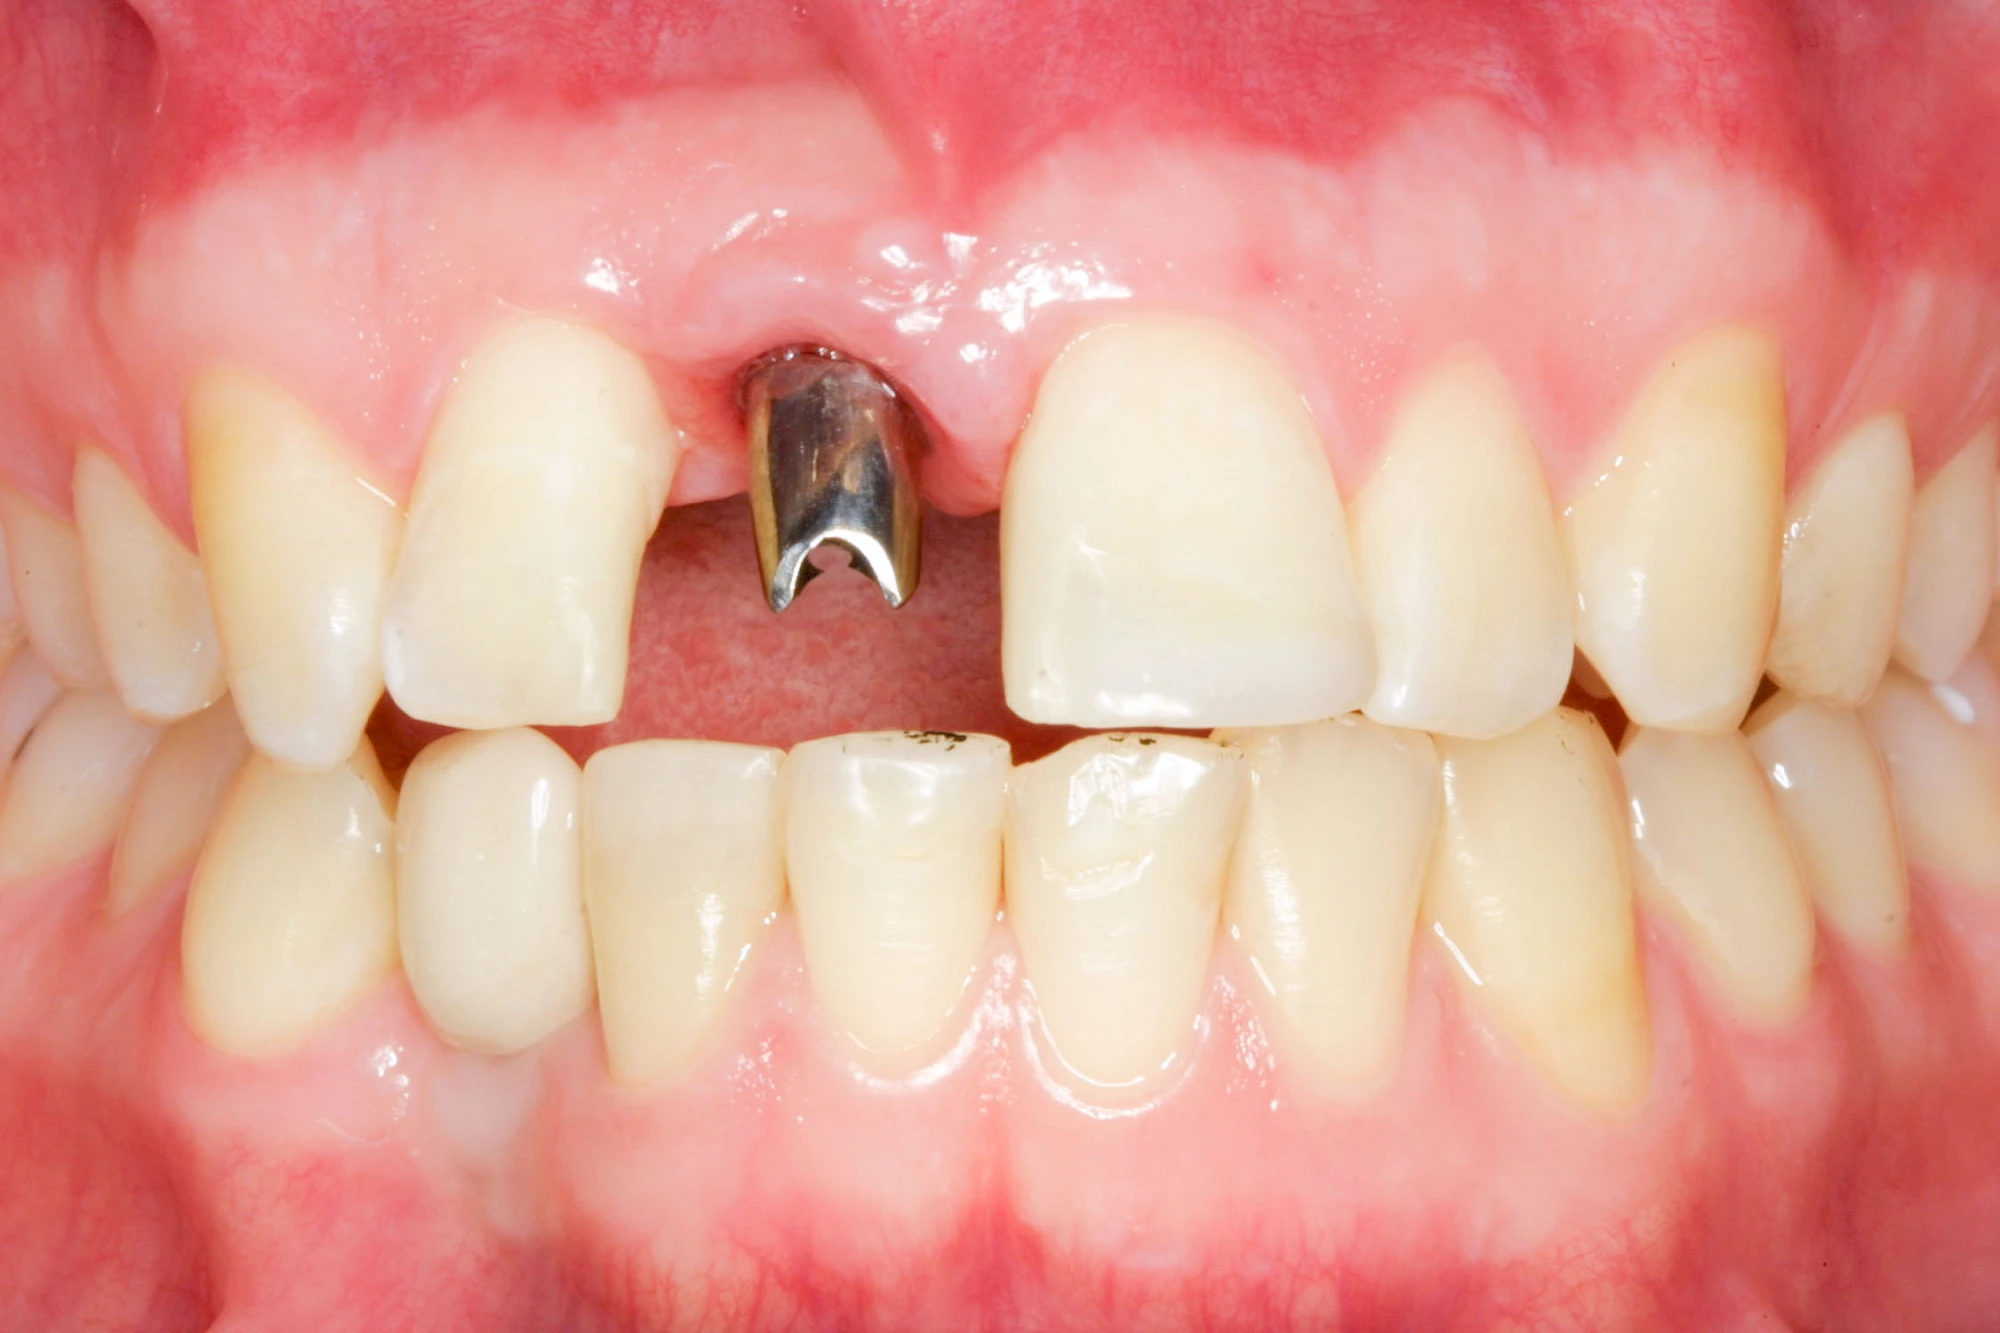

Implantate sind künstliche Zahnwurzeln. Nach einer gewissen Einheilzeit im Knochen (meist 3-6 Monate) erfolgt über einen separaten Aufbau (Abutment) die Befestigung einer Krone bzw. Brücke oder Zahnprothese.

In seltenen Fällen sind Implantate samt Aufbau aus einem Stück gefertigt. Auch gibt es Situationen, die ein Früh- oder sogar eine Sofortbelastung erlauben – dann kann die Einheilzeit der Implantate in den Knochen verkürzt oder sogar gänzlich darauf verzichtet werden.

"Stiftzahn" und "Implantat" ist nicht dasselbe! Bei einem Stiftzahn wird die Zahnkrone mit einem Stift in die noch vorhandene eigene Zahnwurzel zementiert. Ein Implantat im Gegensatz dazu ist selbst die (künstliche) Zahnwurzel, die dann weiter mit einem Zahnersatz versorgt wird.

Fehlen einzelne Zähne und die Nachbarzähne sind unbeschadet oder gut zahnärztlich versorgt, werden immer häufiger Implantate gewählt, um die Lücken zu schließen. Auch bei größeren oder verteilten Lücken, wenn keine herausnehmbare Prothese gewünscht ist, werden Implantate für Kronen- bzw. Brückenversorgungen gesetzt. In Einzelfällen entscheiden sich sogar zahnlose Patienten für eine festsitzende Versorgung auf Implantaten.